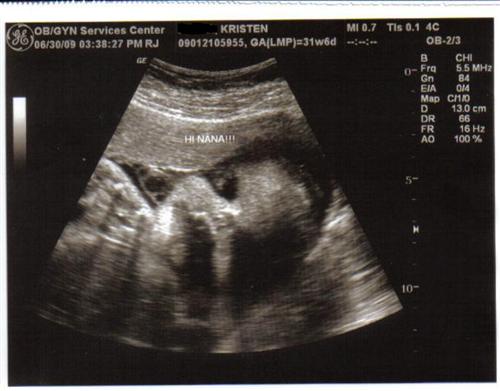

Our little boy is doing very well! He is measuing right on target for 31w6d 4.1lbs & head down!!! The tech said that he will be a 7-8lb baby if I go to term. His amniotic fluid is good but he is getting very cramped, so they would not be shocked to see me go early.

Here are 2 pictures that I love (we got about 8) & what made it so special is my mom got to accompany me & see her grandson in live time & it was her first time experiencing a sono!

So exciting! I'm glad your mom got to share it with you. Love the little "Hi Nana" caption!